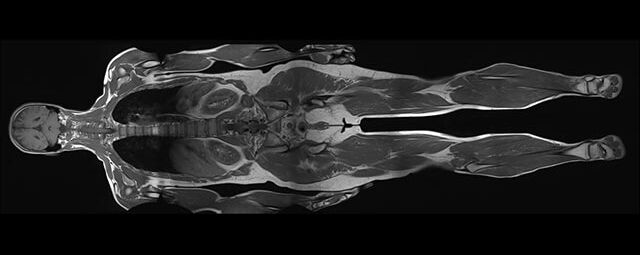

Im Magnetresonanztomographen liegt die zu untersuchende Person in einem starken, homogenen Magnetfeld. Dieses Magnetfeld bewirkt eine gemeinsame Ausrichtung der Wasserstoffprotonen im Körper entlang der Längsachse des Magnetfeldes. Wird nun diesen Teilchen Energie in Form von Radiowellen in einer genau abgegrenzten Frequenz zugeführt, so werden sie aus ihrer ursprünglichen Orientierung abgelenkt.

Die zugeführte Energie wird in gewebespezifischer Weise wieder abgegeben. Ein hochempfindliches Computersystem misst die unterschiedliche Energieabgabe und setzt sie in Bildinformationen um. Jede Körperregion kann somit durch Schnittbilder in allen Raumebenen oder durch dreidimensionale Rekonstruktionen mit einem exzellenten Weichteilkontrast dargestellt werden. Es besteht keine Belastung durch Röntgenstrahlen.